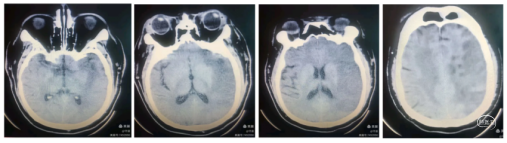

术后情况:患者可睁眼,右下肢自动缩伸,肌力4级,完全性失语状态。

术后12小时:患者意识清楚,能书写表达,失语,右下肢肌力5-,上肢肌力0级。复查CT脑水肿较术前不明显,中线无移位,无出血征象。术后浅淡低密度影较前好转,脑沟脑回可见。